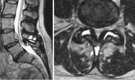

- Risonanza magnetica (MRI) o TAC: Per visualizzare i tessuti molli e i dettagli delle articolazioni. Sono strumenti diagnostici fondamentali per individuare e comprendere le alterazioni anatomiche e funzionali della colonna vertebrale associate alla sindrome faccettale. Evidenziano in particolar modo:

Articolazioni faccettarie ingrossate o irregolari, segno di artrite o degenerazione.

Infiammazione della capsula articolare.

Edema osseo: Un segno di stress o infiammazione delle faccette.

Ispessimento dei legamenti (ligamentum flavum), che può contribuire alla compressione del canale spinale.

Riduzione dello spazio articolare: Indicativa di usura cartilaginea.

Cisti sinoviali: Formazioni piene di liquido che possono comprimere i nervi spinali.